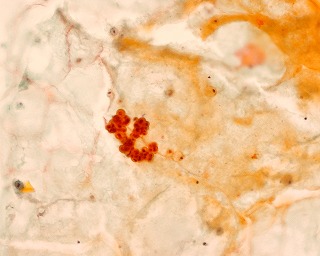

50歳代  女性  乳腺穿刺

*画像をクリックすると拡大写真が見れます。